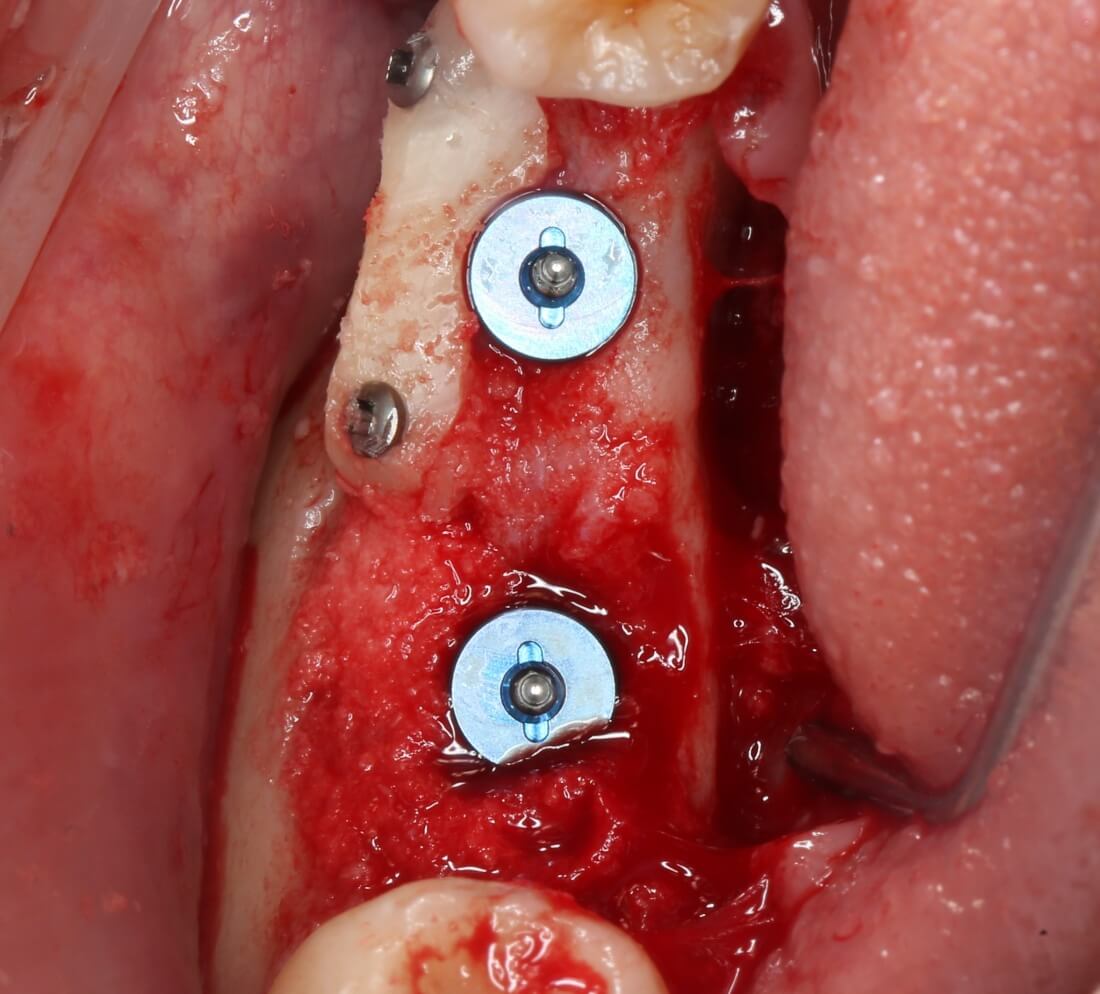

Я зафиксировал костный блок практически без адаптации на несколько винтов. Обрати внимание, что винты находятся в зоне, где не планируется установка имплантатов. Фиксация должна быть надежной, поскольку мне еще предстояла подготовка лунок для имплантатов. Трех винтов для этого вполне достаточно.

Дальнейшая адаптация костного блока свелась к сглаживанию острых краев. После чего я приступил к подготовке лунок и установке имплантатов.

Напомню, что для этой работы я выбрал субкрестальные имплантаты Ankylos C/X. Они прекрасно сочетаются с любым методом остеопластики.

Я не планирую установку супраструктур или коронок, поэтому на уровень первичной стабильности можно положить болт. Даже наоборот — чем меньше крутящий момент при установке, тем лучше. Для имплантатов Ankylos и подобных им, это особенно важно. В общем, момент силы при установке — не более 10-15 Нсм.

Ремарка: имплантаты с предустановленными имплантодержателями хороши тем, что с ними легко контролировать позиционирование имплантатов. В случае с Ankylos С/Х - еще и крутящий момент. Имплантодержатель должен отсоединяться от имплантата с легким щелчком. Если его клинит, и тебе приходится прикладывать для этого усилия, то ты, однозначно, превысил момент силы во время установки имплантата. Следовательно, жди проблем.

Глянем на то, что получилось:

Осталось адаптировать костный блок (убрать острые края), проверить его фиксацию и, при необходимости, добавить винты. Десятисекундное дело.